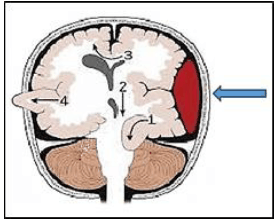

A imagem a seguir evidencia um hematoma cerebral (indicado pela seta) e os principais tipos de herniação cerebral; observe:

Assinale, a seguir, o número correspondente à hérnia de uncus ou uncal.